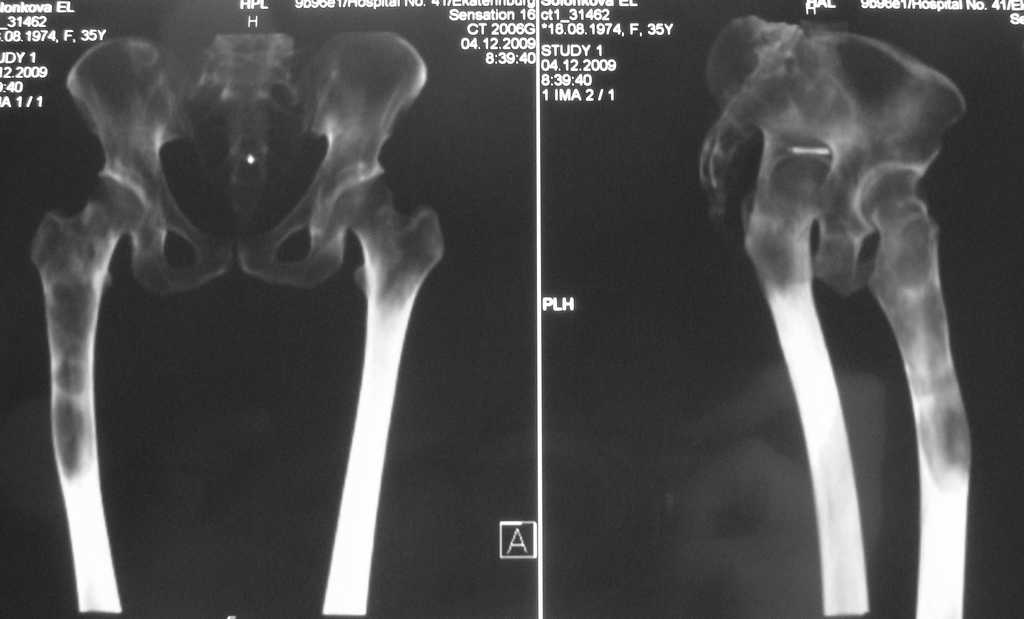

Уважаемые коллеги, доброго времени суток!

Большое спасибо всем, откликнувшимся на сообщение от 17 ноября

"Фиброзная дисплазия". В настоящее время пациентке выполнена

компьютерная томография и открытая биопсия правой бедренной кости с

последующим иммуно-гистохимическим исследованием.

Подтверждается диагноз фиброзной дисплазии без малигнизации.

Хотелось бы услышать мнение коллег относительно тактики дальнейшего

лечения пациентки, в первую очередь, варианты замещения дефекта в

случае резекции патологического очага с учётом обширности поражения.